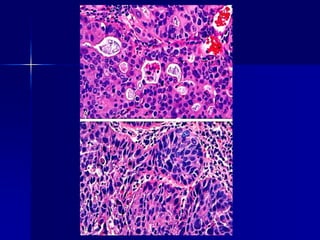

Adenocarcinoma gástrico.

A. Adenocarcinoma de tipo

intestinal compuesto por células

cilíndricas y formadoras de glándulas

que infiltran a través del estroma

desmoplásico.

B.En los tumores infiltrantes,

las células en anillo de sello (difuso)

pueden ser reconocidas por sus grandes

vacuolas de mucina citoplásmica y sus

núcleos delgados falciformes,

desplazados hacia la periferia.

Obsérvese la ausencia de formación de

glándulas